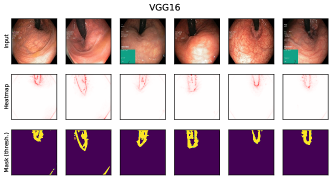

6.4 Spatial Bias Localization

To spatially localize biases in input space with CAVs, we compute local explanations for the element-wise product of latent activations and concept direction (see Eq. 2). We use the controlled artifacts, specifically timestamp (HyperKvasir) and micropscope (ISIC2019) with ground truth concept localization masks for evaluation. We compute (1) the percentage of relevance within the ground truth mask and (2) the Jaccard index, or Intersection over Union (IoU), of the binarized localization mask with the ground truth. In Fig. 9, we report both metrics using CAVs computed on different layers of VGG16 and ResNet50. The layer choice for concept representations is key, as for example middle layers perform better to localize timestamps and earlier layers are more effective to localize the microscope. In comparison with Fig.7, we find that the optimal layer for bias localization may differ from the one for sample retrieval. Interestingly, the IoU for the microscope artifact is consistently low, as models primarily focus on the border of the circle instead of the entire area, as indicated by qualitative results in Appendix A.6.3. Unlike artifact relevance, the IoU metric also measures how much of the expected areas the computed mask does not cover.